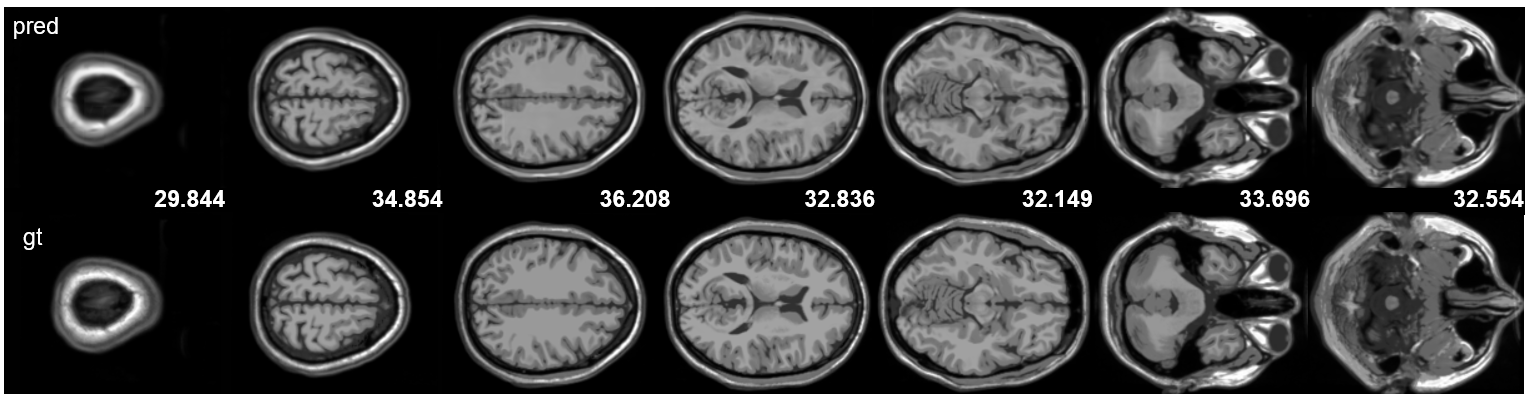

For Cardiac MRI, the quantitative results are summarized in Table 3. Figure 3 presents detailed reconstruction results on the coronal plane, while results for the axial and sagittal plane are reported in Appendix 7. The renderings accurately capture details such as the heart chambers and vessels.

Refer to caption

Figure 3: Cardiac MR reconstructions (coronal view).

Figure 7 shows the reconstruction results of cardiac MRI images in different anatomical planes (axial and sagittal). It can be observed that the model successfully reconstructs cardiac structures across different planes, accurately depicting anatomical details such as the heart chambers, myocardium, and major vessels.

Figure 7: Cardiac MR reconstructions in axial (top) and sagittal (bottom) planes.

*The 2nd axial slice and the 5th sagittal slice showed abnormally low PSNR (25.117 dB and 25.030 dB). Applying affine normalization to match the ground truth’s mean and variance raised PSNR to 35.15 dB and 32.24 dB, respectively. This suggests that the degradation might stems from bias field effects and brightness drift in the training data, rather than structural reconstruction errors.